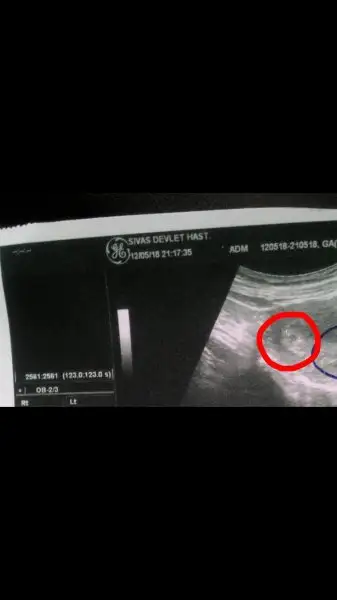

Çok şükür darısı kalp atışını duymayı nasip etsin rabbim darısı bizlerehamd olsun keseyi gorduk bugun bel agrilarm var diye gittim acile kanda guzel artmis Rabbim isteyen bekleyen herkese nasip etsin insallah bebegi ve kalp atisinida duyariz hayirlisiyla